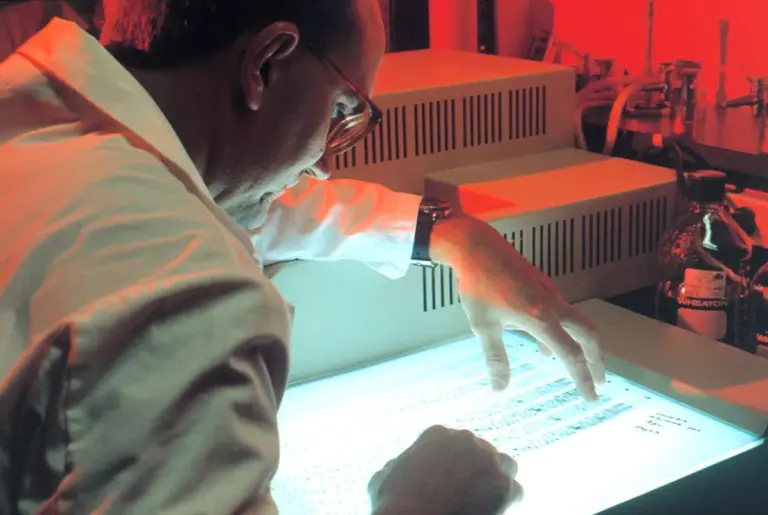

The COVID-19 pandemic highlighted the importance of expert opinions in shaping public health policies and responses. Epidemiologists, virologists, and healthcare experts guided government actions and public awareness campaigns, demonstrating how critical expert advice can be in times of crisis. Similarly, in the technological realm, cybersecurity experts are pivotal in safeguarding information and systems amid increasing threats. According to a recent report by the World Economic Forum, 82% of organisations recognise the need for expert guidance to navigate complex digital transformations.